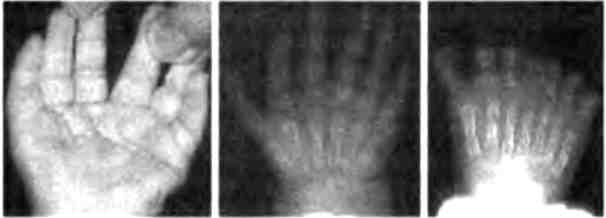

В коллекции Бэтсона присутствовали и человеческие уродства: здесь были люди с дополнительными ребрами, человек с лишними сосками, удивительная левая рука с восемью пальцами, расположенными симметричным образом, а также люди с лишними пальцами на одной или обеих руках (рис. 2.7). Этот последний дефект, называемый полидактилией, встречается не так уж редко, примерно у 5-17 из 10 000 живорожденных детей.

Иллюстрация к книге — Бесконечное число самых прекрасных форм [img_22.jpg]

Рис. 2.7. Полидактилия у человека. Из книги У. Бэтсона "Материалы по изучению изменчивости", 1894.

Степень выраженности полидактилии бывает разной — от кожного выроста со стороны большого пальца или мизинца до дополнительного ногтя, отдельной фаланги или целого пальца. Дополнительные пальцы могут быть отделены от остальных или срощены с ними. В последнем случае этот дефект называют синполидактилией. В некоторых случаях дополнительные пальцы возникают симметрично на двух руках и двух ногах (рис. 2.8).